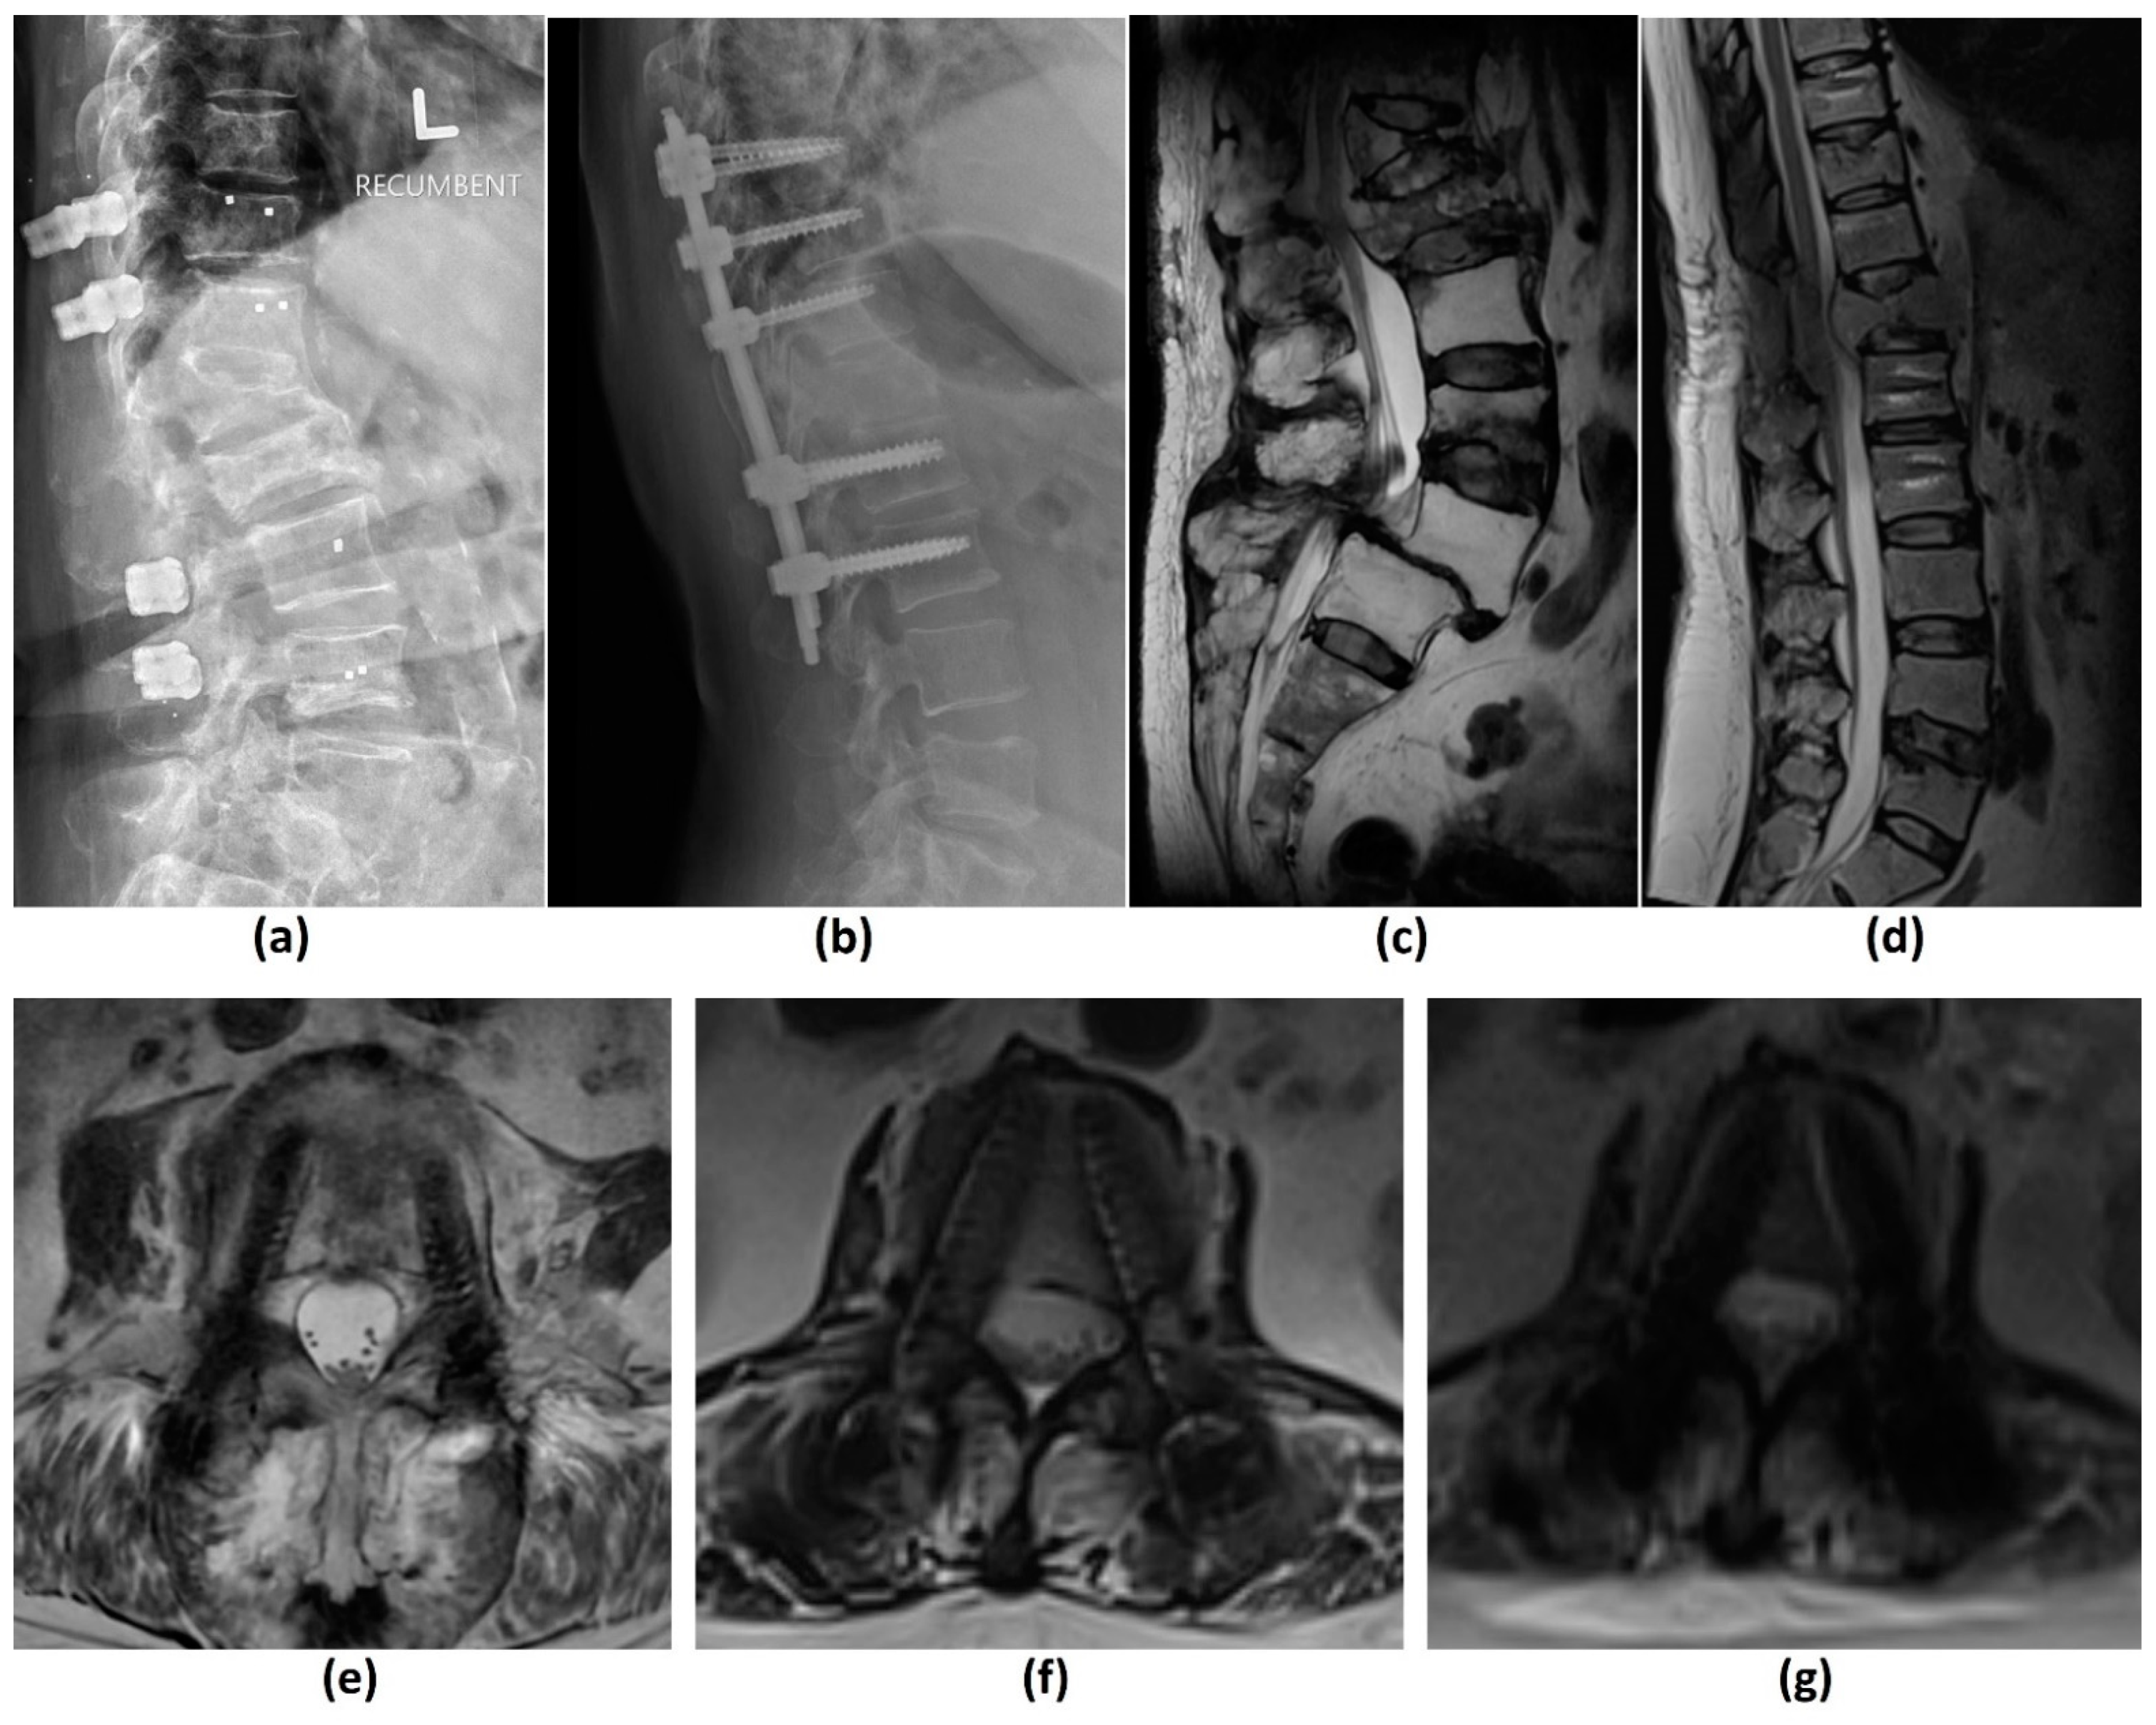

- Stradiotti, P.; Curti, A.; Castellazzi, G.; Zerbi, A. Metal-related artifacts in instrumented spine. Techniques for reducing artifacts in CT and MRI: State of the art. Eur. Spine J. 2009, 18 (Suppl. 1), 102–108. [Google Scholar] [CrossRef] [Green Version]

- Krätzig, T.; Mende, K.C.; Mohme, M.; Kniep, H.; Dreimann, M.; Stangenberg, M.; Westphal, M.; Gauer, T.; Eicker, S.O. Carbon fiber-reinforced PEEK versus titanium implants: An in vitro comparison of susceptibility artifacts in CT and MR imaging. Neurosurg. Rev. 2021, 44, 2163–2170. [Google Scholar] [CrossRef]

- Jungmann, P.M.; Agten, C.A.; Pfirrmann, C.W.; Sutter, R. Advances in MRI around metal. J. Magn. Reson. Imaging 2017, 46, 972–991. [Google Scholar] [CrossRef]

- Talbot, B.S.; Weinberg, E.P. MR Imaging with Metal-suppression Sequences for Evaluation of Total Joint Arthroplasty. Radiographics 2016, 36, 209–225. [Google Scholar] [CrossRef]

- Do, T.D.; Sutter, R.; Skornitzke, S.; Weber, M.A. CT and MRI Techniques for Imaging Around Orthopedic Hardware. Rofo 2018, 190, 31–41. [Google Scholar] [CrossRef] [PubMed] [Green Version]

- Kumar, N.; Lopez, K.G.; Alathur Ramakrishnan, S.; Hallinan, J.T.P.D.; Fuh, J.Y.H.; Pandita, N.; Madhu, S.; Kumar, A.; Benneker, L.M.; Vellayappan, B.A. Evolution of materials for implants in metastatic spine disease till date—Have we found an ideal material? Radiother Oncol. 2021, 163, 93–104. [Google Scholar] [CrossRef] [PubMed]

- Kumar, N.; Ramakrishnan, S.A.; Lopez, K.G.; Madhu, S.; Ramos, M.R.D.; Fuh, J.Y.H.; Hallinan, J.; Nolan, C.P.; Benneker, L.M.; Vellayappan, B.A. Can Polyether Ether Ketone Dethrone Titanium as the Choice Implant Material for Metastatic Spine Tumor Surgery? World Neurosurg. 2021, 148, 94–109. [Google Scholar] [CrossRef] [PubMed]

- Zimel, M.N.; Hwang, S.; Riedel, E.R.; Healey, J.H. Carbon fiber intramedullary nails reduce artifact in postoperative advanced imaging. Skelet. Radiol. 2015, 44, 1317–1325. [Google Scholar] [CrossRef]

- Osterhoff, G.; Huber, F.A.; Graf, L.C.; Erdlen, F.; Pape, H.C.; Sprengel, K.; Guggenberger, R. Comparison of metal artifact reduction techniques in magnetic resonance imaging of carbon-reinforced PEEK and titanium spinal implants. Acta Radiol. 2021, 2841851211029077. [Google Scholar] [CrossRef]